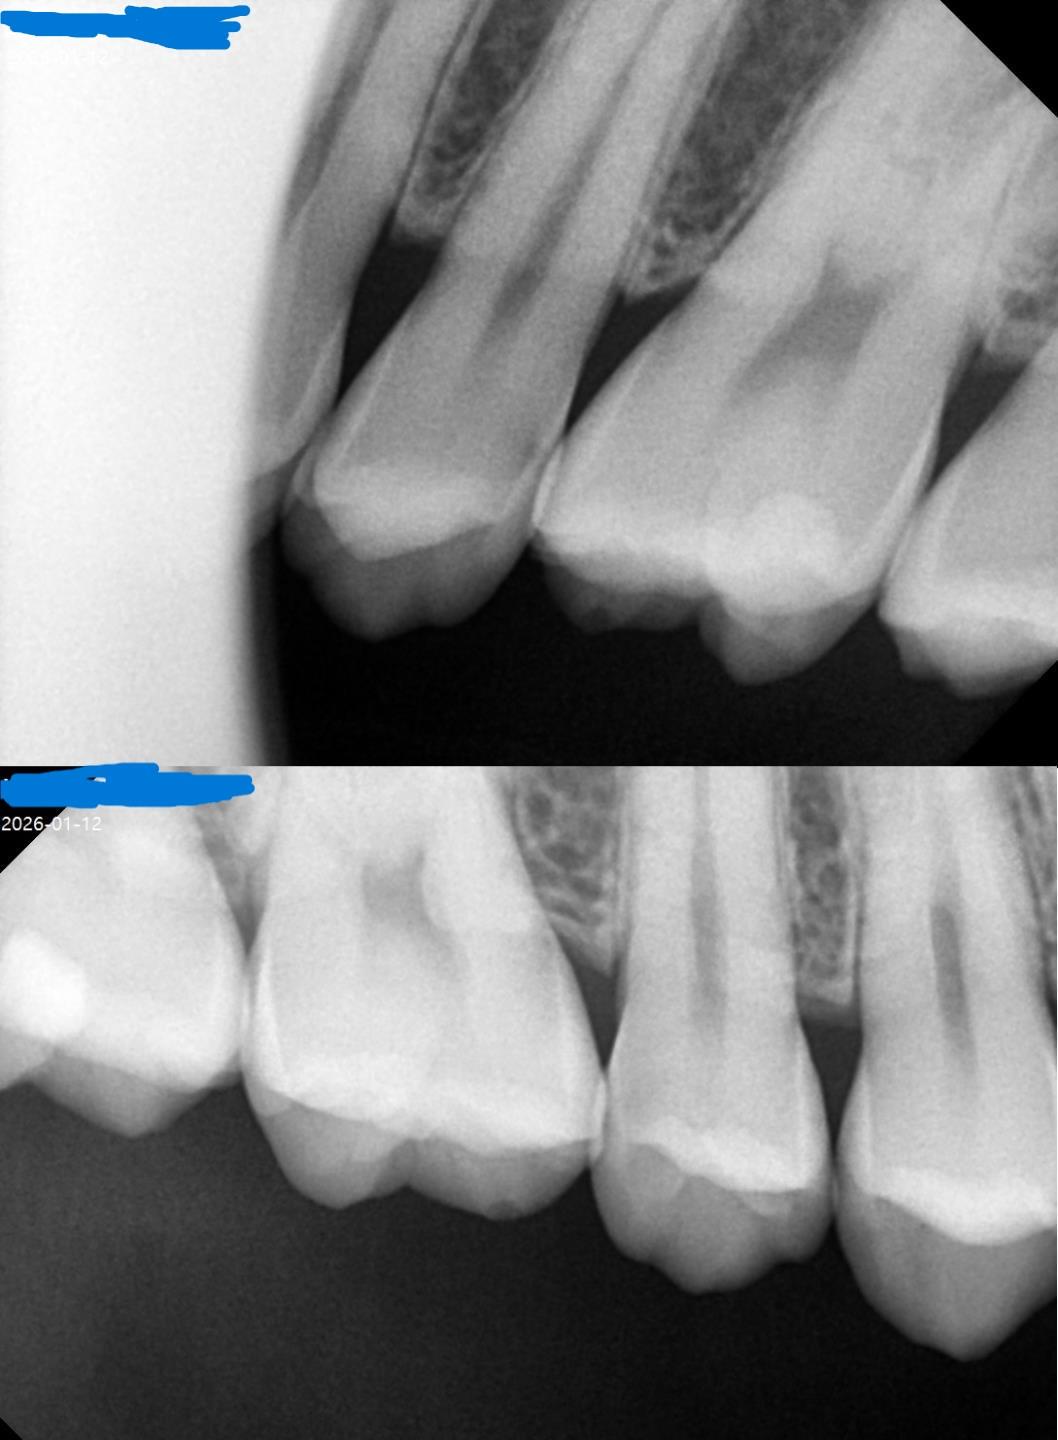

엑스레이 찍었어요 충치가 있다고 하는데 과잉진료인지 궁금해요

첫 번째 사진 치과는 스케일링 받으면서 xray도 같이 찍었는데 어금니 양쪽에 인접면 충치 인레이 2개를 해야된다고 해서

두 번째 사진 치과를 갔는데 오른쪽 어금니 인레이3개 왼쪽 인레이 1개 아랫니 레진 1개를 부르더라고요

둘다 과잉 진료인가요? 서로 진료가 달라서 의심스럽고 통증도 없구요 두 번째 사진은 치아 사진도 보여주면서 여기 검은 색 인접면 보여주긴 했는데 솔직히 뭐가 뭔지 모르겠고 통증도 없고 20대인데 굳이 치아 절삭이 필요한가 싶어서 문의드려요

• 1번 째 사진

• 2번 째 사진

2. 인접면 충치가 위 엑스레이상에서 보이는 상태입니다 엑스레이상 보이는 충치는 이미 진행이 된 충치여서 그대로 둔다고 나아지고 그런건 없습니다.